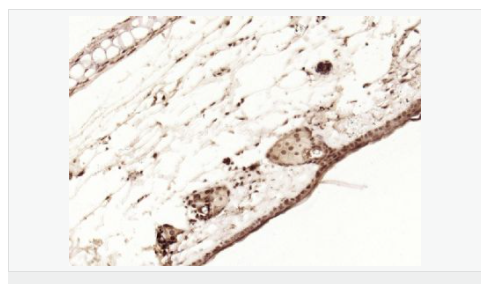

| 產(chǎn)品應(yīng)用 | WB=1:1000-2000 ELISA=1:1000-5000 IHC-P=1:100-500 IHC-F=1:100-500 Flow-Cyt=1ug/Test ICC=1:100-500 IF=1:100-500 (石蠟切片需做抗原修復(fù)) not yet tested in other applications. optimal dilutions/concentrations should be determined by the end user. |